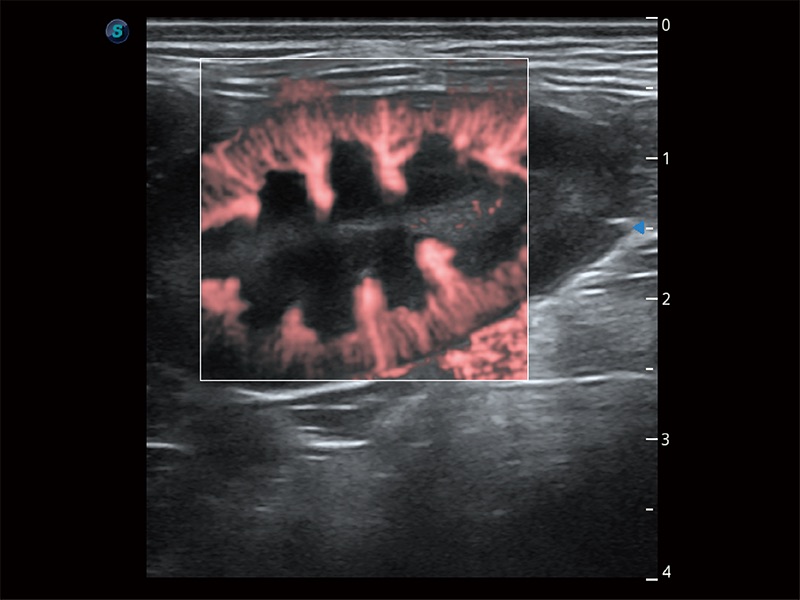

(犬)肠道

(犬)胎儿主动脉弓立体血流